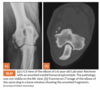

Q

3.5m Yorkie

A

lateral humeral condylar fracture - see its caudal displacement, superimposed over the cranial ulna.